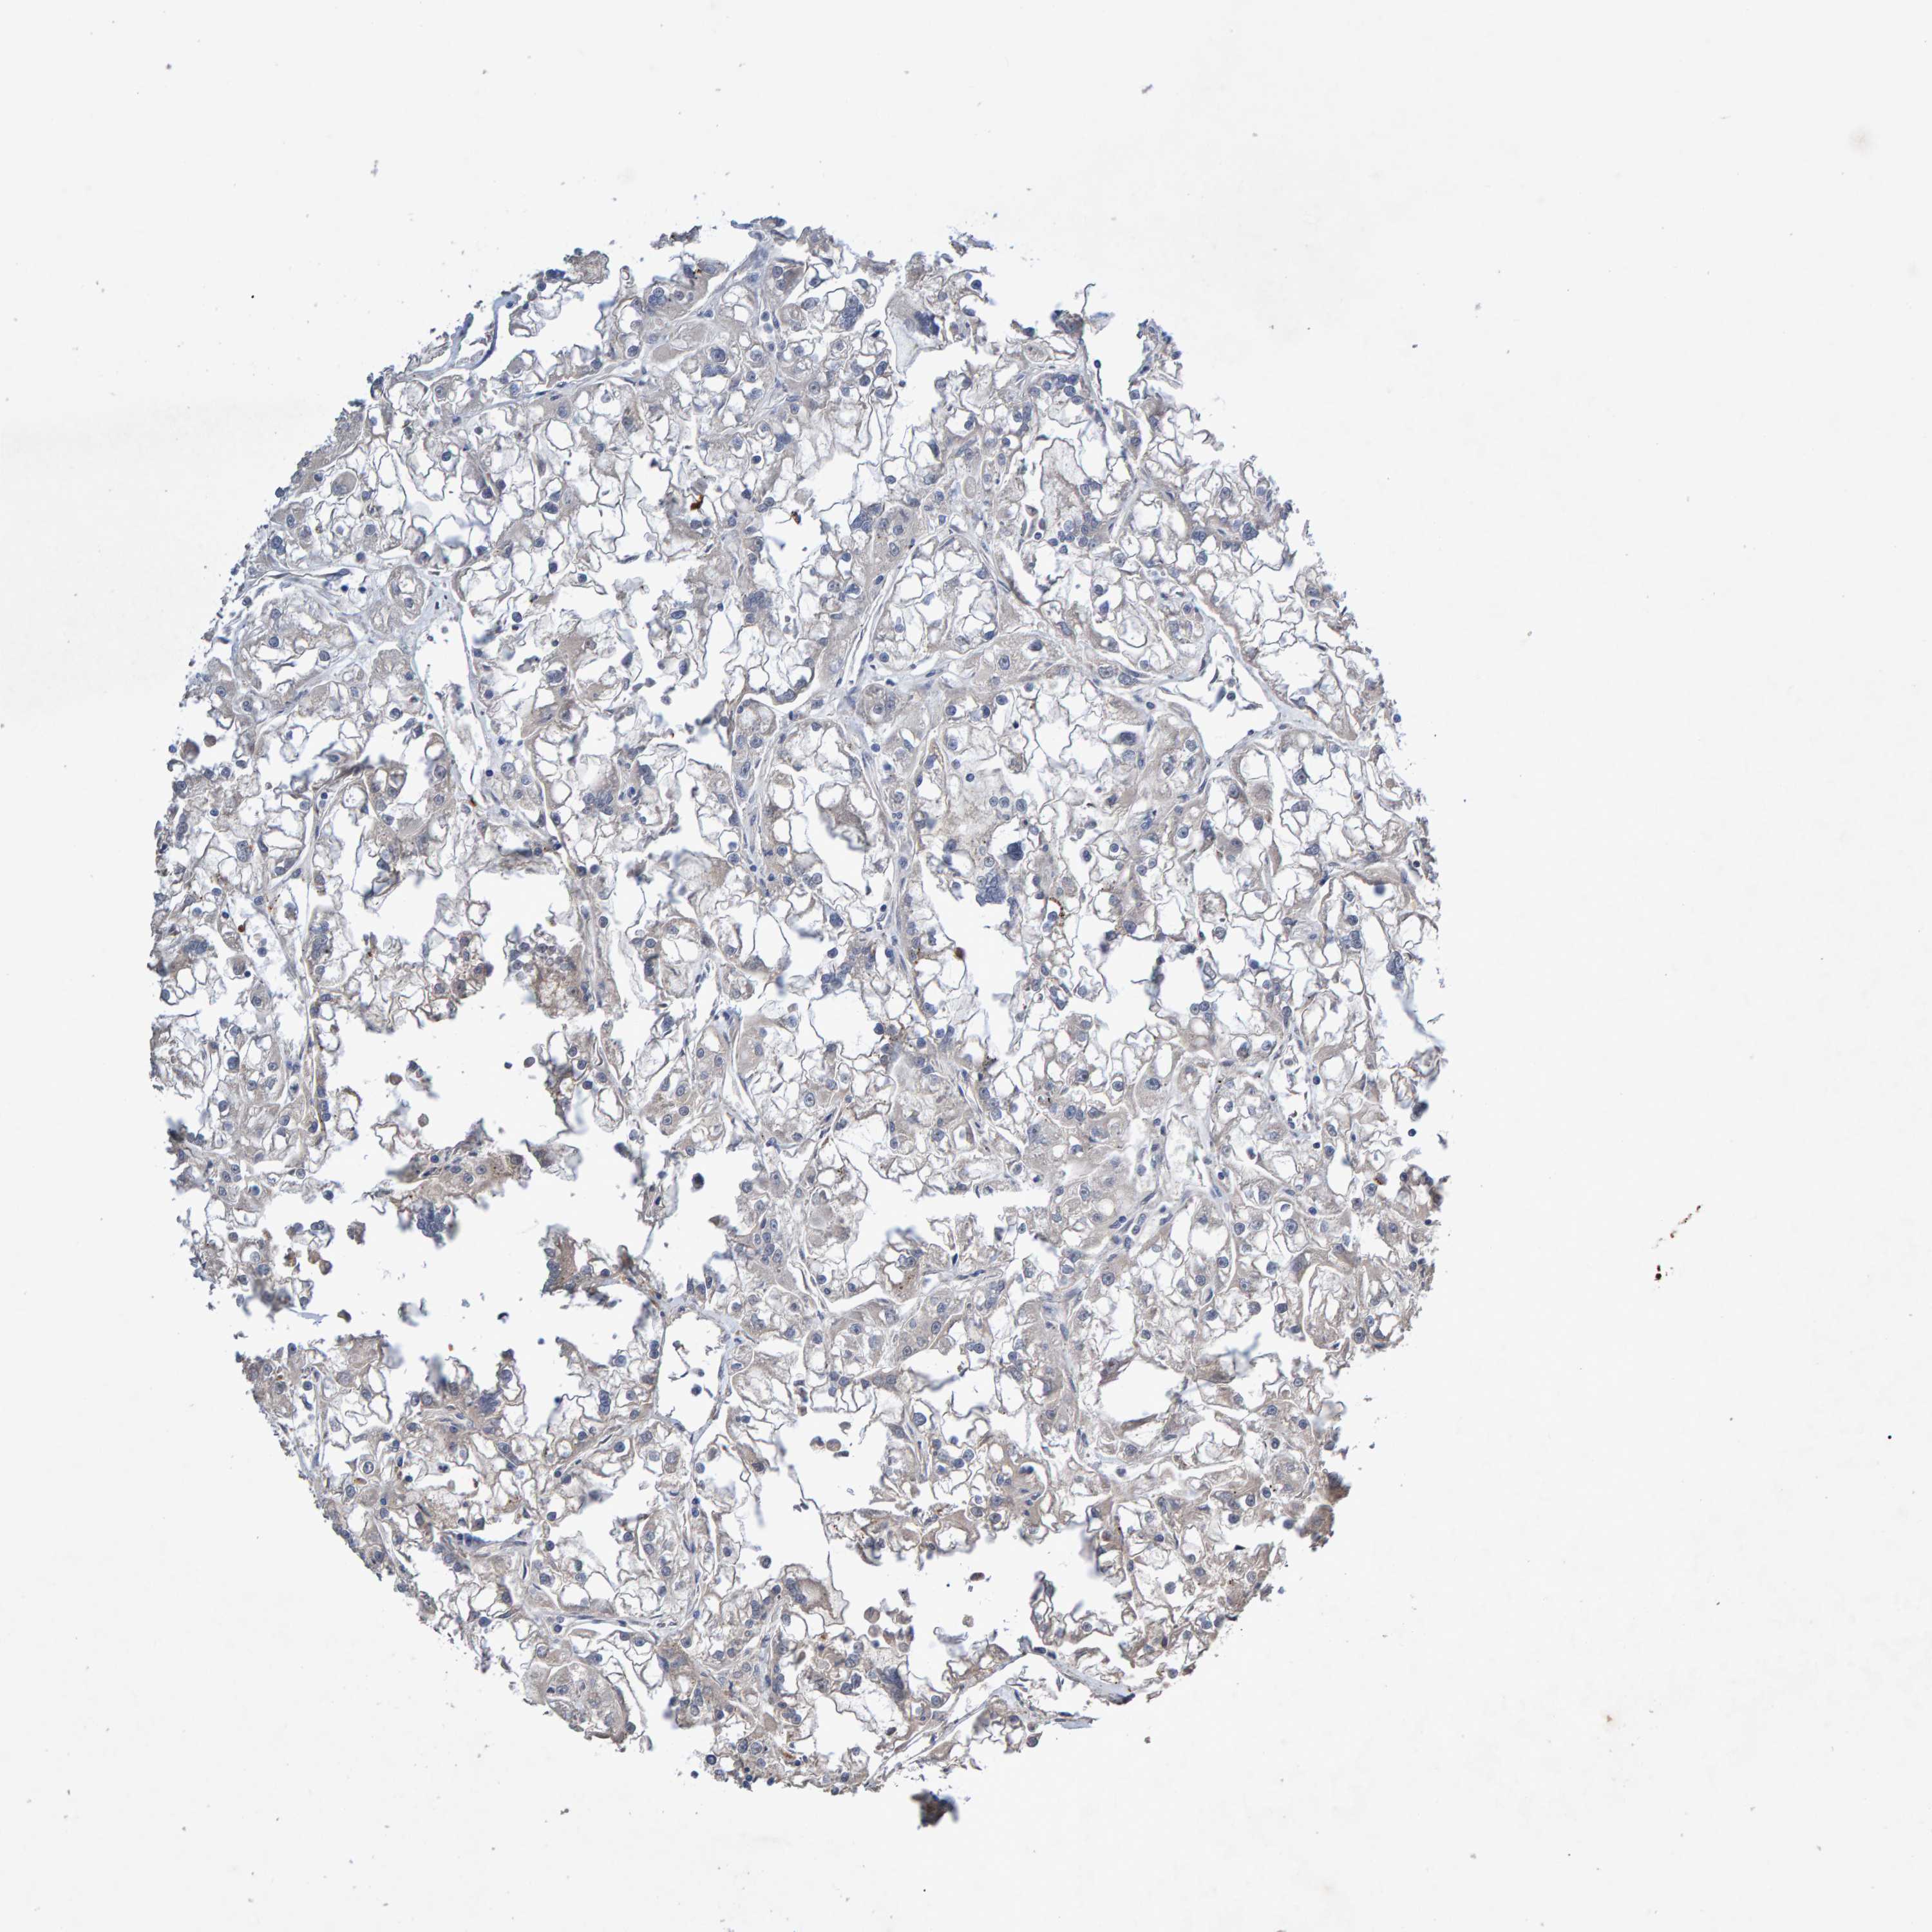

KIDNEY RENAL CLEAR CELL CARCINOMA (TCGA) - Interactive survival scatter ploti

The Survival Scatter plot shows the clinical status (i.e. dead or alive) for all individuals in the patient cohort, based on the same data that underlies the corresponding Kaplan-Meier plots. Patients that are alive at last time for follow-up are shown in blue and patients who have died during the study are shown in red.

The x-axis shows the expression levels (FPKM) of the investigated gene in the tumor tissue at the time of diagnosis. The y-axis shows the follow-up time after diagnosis (years). Both axes are complimented with kernel density curves demonstrating the data density over the axes. The top density plot shows the expression levels (FPKM) distribution among dead (red) and alive patients (blue). The right density plot shows the data density of the survived years of dead patients with high and low expression levels respectively, stratified using the cutoff indicated by the vertical dashed line through the Survival Scatter plot. This cutoff is automatically defined based on the FPKM cutoff that minimizes the p-score. The cutoff can be changed by dragging the vertical line or by entering a cutoff value in the square labeled "Current cut-off".

Under the Survival Scatter plot the p-score landscape (black curve; left axis) is shown together with dead median separation (red curve; right axis). Dead median separation is the difference in median mRNA expression between patients who have died with high and low expression, respectively. It is calculated as follows: median FPKM expression of dead patients with high expression - median FPKM expression of dead patients with low expression. This is intended to aid the user in visually exploring custom cutoffs and the associated p-scores and dead median separation.

Individual patient data is displayed and can be filtered by clicking on one or more of the category buttons on the top of the page. Categories describing expression level and patient information include: high, low, alive, dead, female, male and tumor stages. The scale of the x-axis can be toggled between linear and log-scale by clicking on the "x log" button. Mouse-over function shows TCGA ID, patient information and mRNA expression (FPKM) for each patient.

& Survival analysisi

Kaplan-Meier plots summarize results from analysis of correlation between mRNA expression level and patient survival. Patients were divided based on level of expression into one of the two groups "low" (under cut off) or "high" (over cut off). X-axis shows time for survival (years) and y-axis shows the probability of survival, where 1.0 corresponds to 100 percent.

EFR3A is potential prognostic, high expression is favorable in Kidney Renal Clear Cell Carcinoma (TCGA)

Best expression cut offi

Based on the FPKM value of each gene, patients were classified into two groups and association between prognosis (survival) and gene expression (FPKM) was examined. The best expression cut-off refers the FPKM value that yields maximal difference with regard to survival between the two groups at the lowest log-rank P-value. Best expression cut-off was selected based on survival analysis .

When clicking on this number, the vertical dashed line indicating cut-off, the interactive survival plot, and the Kaplan-Meier curve will be adjusted to show results based on the best expression cut-off.

: 20.32

TCGA RNA samplesi

RNA-seq data is reported as average FPKM (number Fragments Per Kilobase of exon per Million reads), generated by the The Cancer Genome Atlas (TCGA) .

Normal distribution across the dataset is visualized with box plots, shown as median and 25th and 75th percentiles. Points are displayed as outliers if they are above or below 1.5 times the interquartile range. FPKM values of the individual samples are presented next to the box plot.

Average pTPM 26.6

Number of samples 521